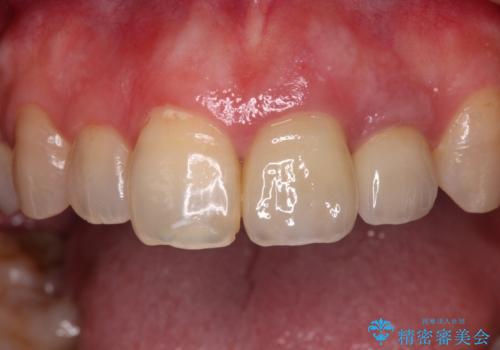

仮歯を装着した時点で、口元が気にならなくなったので、患者様が感じていた違和感の原因は変色した前から2番目の歯であったと思われます。

形態や色彩が左右対称となるように仕上がり、患者様には大変満足していただきました。